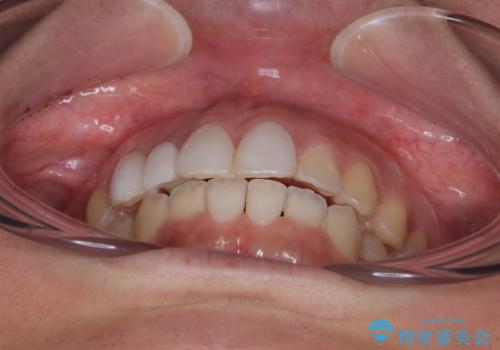

前歯のデコボコが気になる インビザラインによる矯正治療

- 上下前歯のデコボコを気にして来院された患者様です。

インビザラインによる上下歯列の拡大と、IPR(歯と歯の間を削る)にるスペースの獲得により、前歯のデコボコを改善することとしました。

下顎前歯は後戻りを起こしやすいため、舌側を細いワイヤーで固定し、マウスピース型リテーナーで保定を行うこととしました。